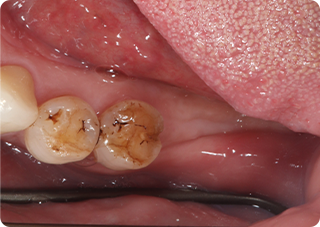

精密根管治療③

術前

| 主訴 | 奥歯で噛むと痛い |

| 治療期間/回数 | 1ヵ月、4回 |

| 価格(税込) | 88,000円(税込) |

| リスク・副作用 | 病変再発、歯根破折の可能性 |

| ポイント | う蝕検知液を用い、むし歯の取り残しが無いようにし、ラバーダム防湿を行い、無菌的に根管治療を行った。根管充填材は、殺菌作用の強い保険適応外のMTAセメントを使用した。 |